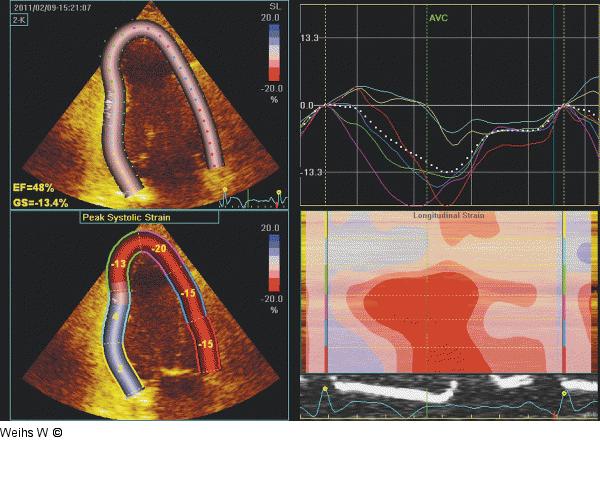

Abbildung 8: Strain-Analyse Zweidimensionale "Strain"-Analyse im 2-Kammerschnitt. Die Werte entsprechen einer Dyskinesie (positive Werte) in den basalen und mittleren inferioren Segmenten sowie einer normalen Deformierung in den anterioren Segmenten. |

Zweidimensionale "Strain"-Analyse im 2-Kammerschnitt. Die Werte entsprechen einer Dyskinesie (positive Werte) in den basalen und mittleren inferioren Segmenten sowie einer normalen Deformierung in den anterioren Segmenten. |